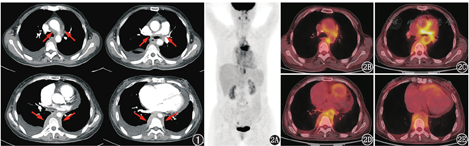

患者女,55岁,主诉胸闷、气短、下肢水肿6个月余。外院超声心动图提示左右肺动脉狭窄,左肺动脉最窄处约3.0 mm,压差为62 mmHg(1 mmHg=0.133 kPa),右肺动脉最窄处约4.1 mm,压差为61 mmHg,伴右心增大、三尖瓣返流、心包积液。胸部CT提示纵隔肿物,包绕主动脉弓、降主动脉及肺动脉等纵隔多根大血管,受累血管管腔狭窄。当地医院行心包积液穿刺,引流物为黄色液体,具体不详。外院遂行后纵隔肿物穿刺,病理为纤维组织增生伴胶原化及淋巴样细胞浸润,可见神经纤维及神经节细胞。患者为求进一步诊治入住本院,入院后实验室检查提示血、尿、便常规大致正常,超敏C反应蛋白增高,为53.65(括号内为正常参考值范围,下同:<3.0) mg/L,糖类抗原(carbohydrate antigen, CA)125及神经元特异性烯醇化酶(neuron specific enolase, NSE)升高,分别为97.5(0~35.0) kU/L与18.2(0~16.3) μg/L,其余肿瘤标志物正常;血管炎相关自身抗体及抗核抗体均为阴性。复查胸部增强CT可见中、后纵隔软组织影,平扫密度均匀,增强扫描动脉期呈轻中度强化,其包绕升主动脉、主动脉弓、降主动脉、肺动脉干及双侧肺动脉,受累范围向上达主动脉弓分支近端血管,向下沿椎旁延伸至膈肌脚水平,致双侧肺动脉主干局部重度狭窄(图1)。临床考虑为恶性病变可能,之后再次行后纵隔肿物穿刺,病理可见玻璃样变增生的梭形细胞,结合免疫组织化学考虑为增生的肌纤维母细胞。临床为评估纵隔占位的良恶性、探查病灶范围,行18F-脱氧葡萄糖(fluorodeoxyglucose, FDG)PET/CT显像。18F-FDG PET/CT显像可见增强CT所示纵隔不规则软组织密度影代谢不均匀增高,以双侧肺动脉周围及后纵隔胸椎两侧为著,最大标准摄取值(maximum standardized uptake value, SUVmax)为7.4(图2)。

本例影像学的主要特点:(1)病灶分布上,主要位于中、后纵隔,前纵隔未见受累;(2)形态方面,病变位于血管周围,与血管分界不清,受累血管明显狭窄,沿血管走形呈条片状表现,而未见明显的结节、肿物;(3)病灶密度较均匀,未见明显囊变、出血及钙化影,增强扫描呈轻中度强化;(4)病变FDG代谢增高但不均匀,肺动脉干周围病灶代谢程度明显增高,而其余部位代谢程度则相对略低。不同的FDG代谢活性与肿瘤细胞的分化程度、不同程度的纤维组织增生、炎性细胞的比例和活跃程度等有关,这可能说明病变内部性质不一。